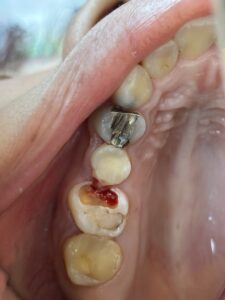

金属アレルギーの原因になる得る、銀歯を白くしたいという患者さんがいますが、保険適応でCADCAMやハイブリッドセラミックで治療してくれる歯科医院が、相変わらず少ないと言う患者様が来院されますね。

セラミックインレーやジルコニアクラウンもおすすめです。これらは自費ですが。

違いや比較としては 保険のは年数が経過すると 劣化したり変色する 欠けたり割れたりする可能性があります。